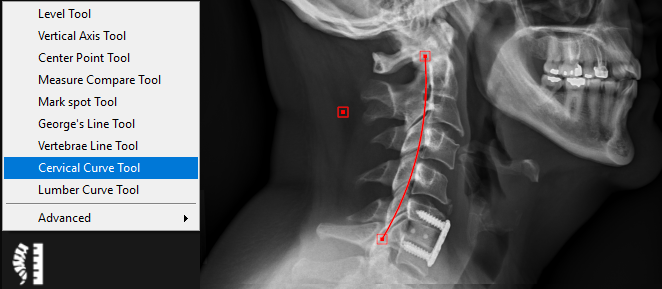

9.5.8. Cervical Curve Tool

The cervical curve tool is used to draw a curve between two points based on the radius of a circle including those points. Follow the instructions below to use this tool:

1.      Select the ‘Cervical Curve Tool’ from the chiropractic toolbox.

2.      Click on the image to set the starting point of the curve.

3.      Click to set the ending point of the curve.

4.      Click to set the final point on either the right or left side of the curve to determine the direction of the curve.

A curve will be drawn based on the radius of a circle including those points (default radius is 17cm):